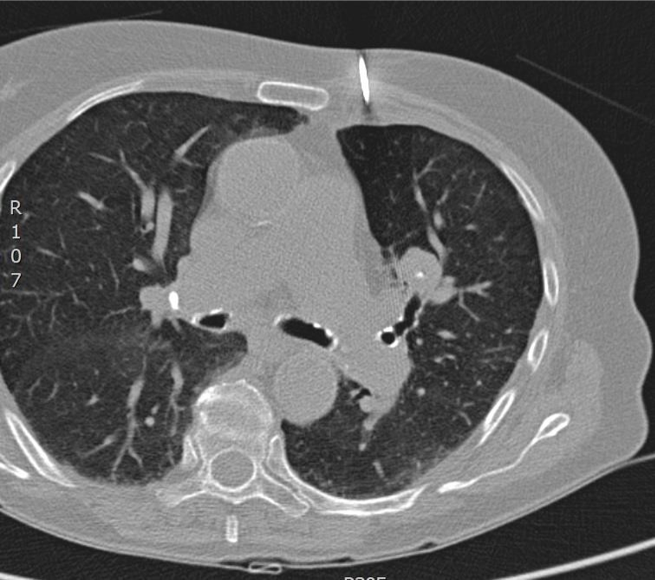

第一次CT扫描:观察引导针穿刺的方向和平面是否和靶病变一致(注意穿刺针的针尖不能停留在脏层胸膜表面,避免气胸)

第二次CT扫描:观察穿刺针在肺内的方向与平面是否与靶病变一致(注意每次针前进的距离是剩余针道的一半,以便随时纠正穿刺针前进的方向和水平)

引导针到病变的边缘

置换活检针

活检针进入病灶内活检,注意后方,针尖不要超过病灶的后界

拔针后显示沿针道少量肺实质出血